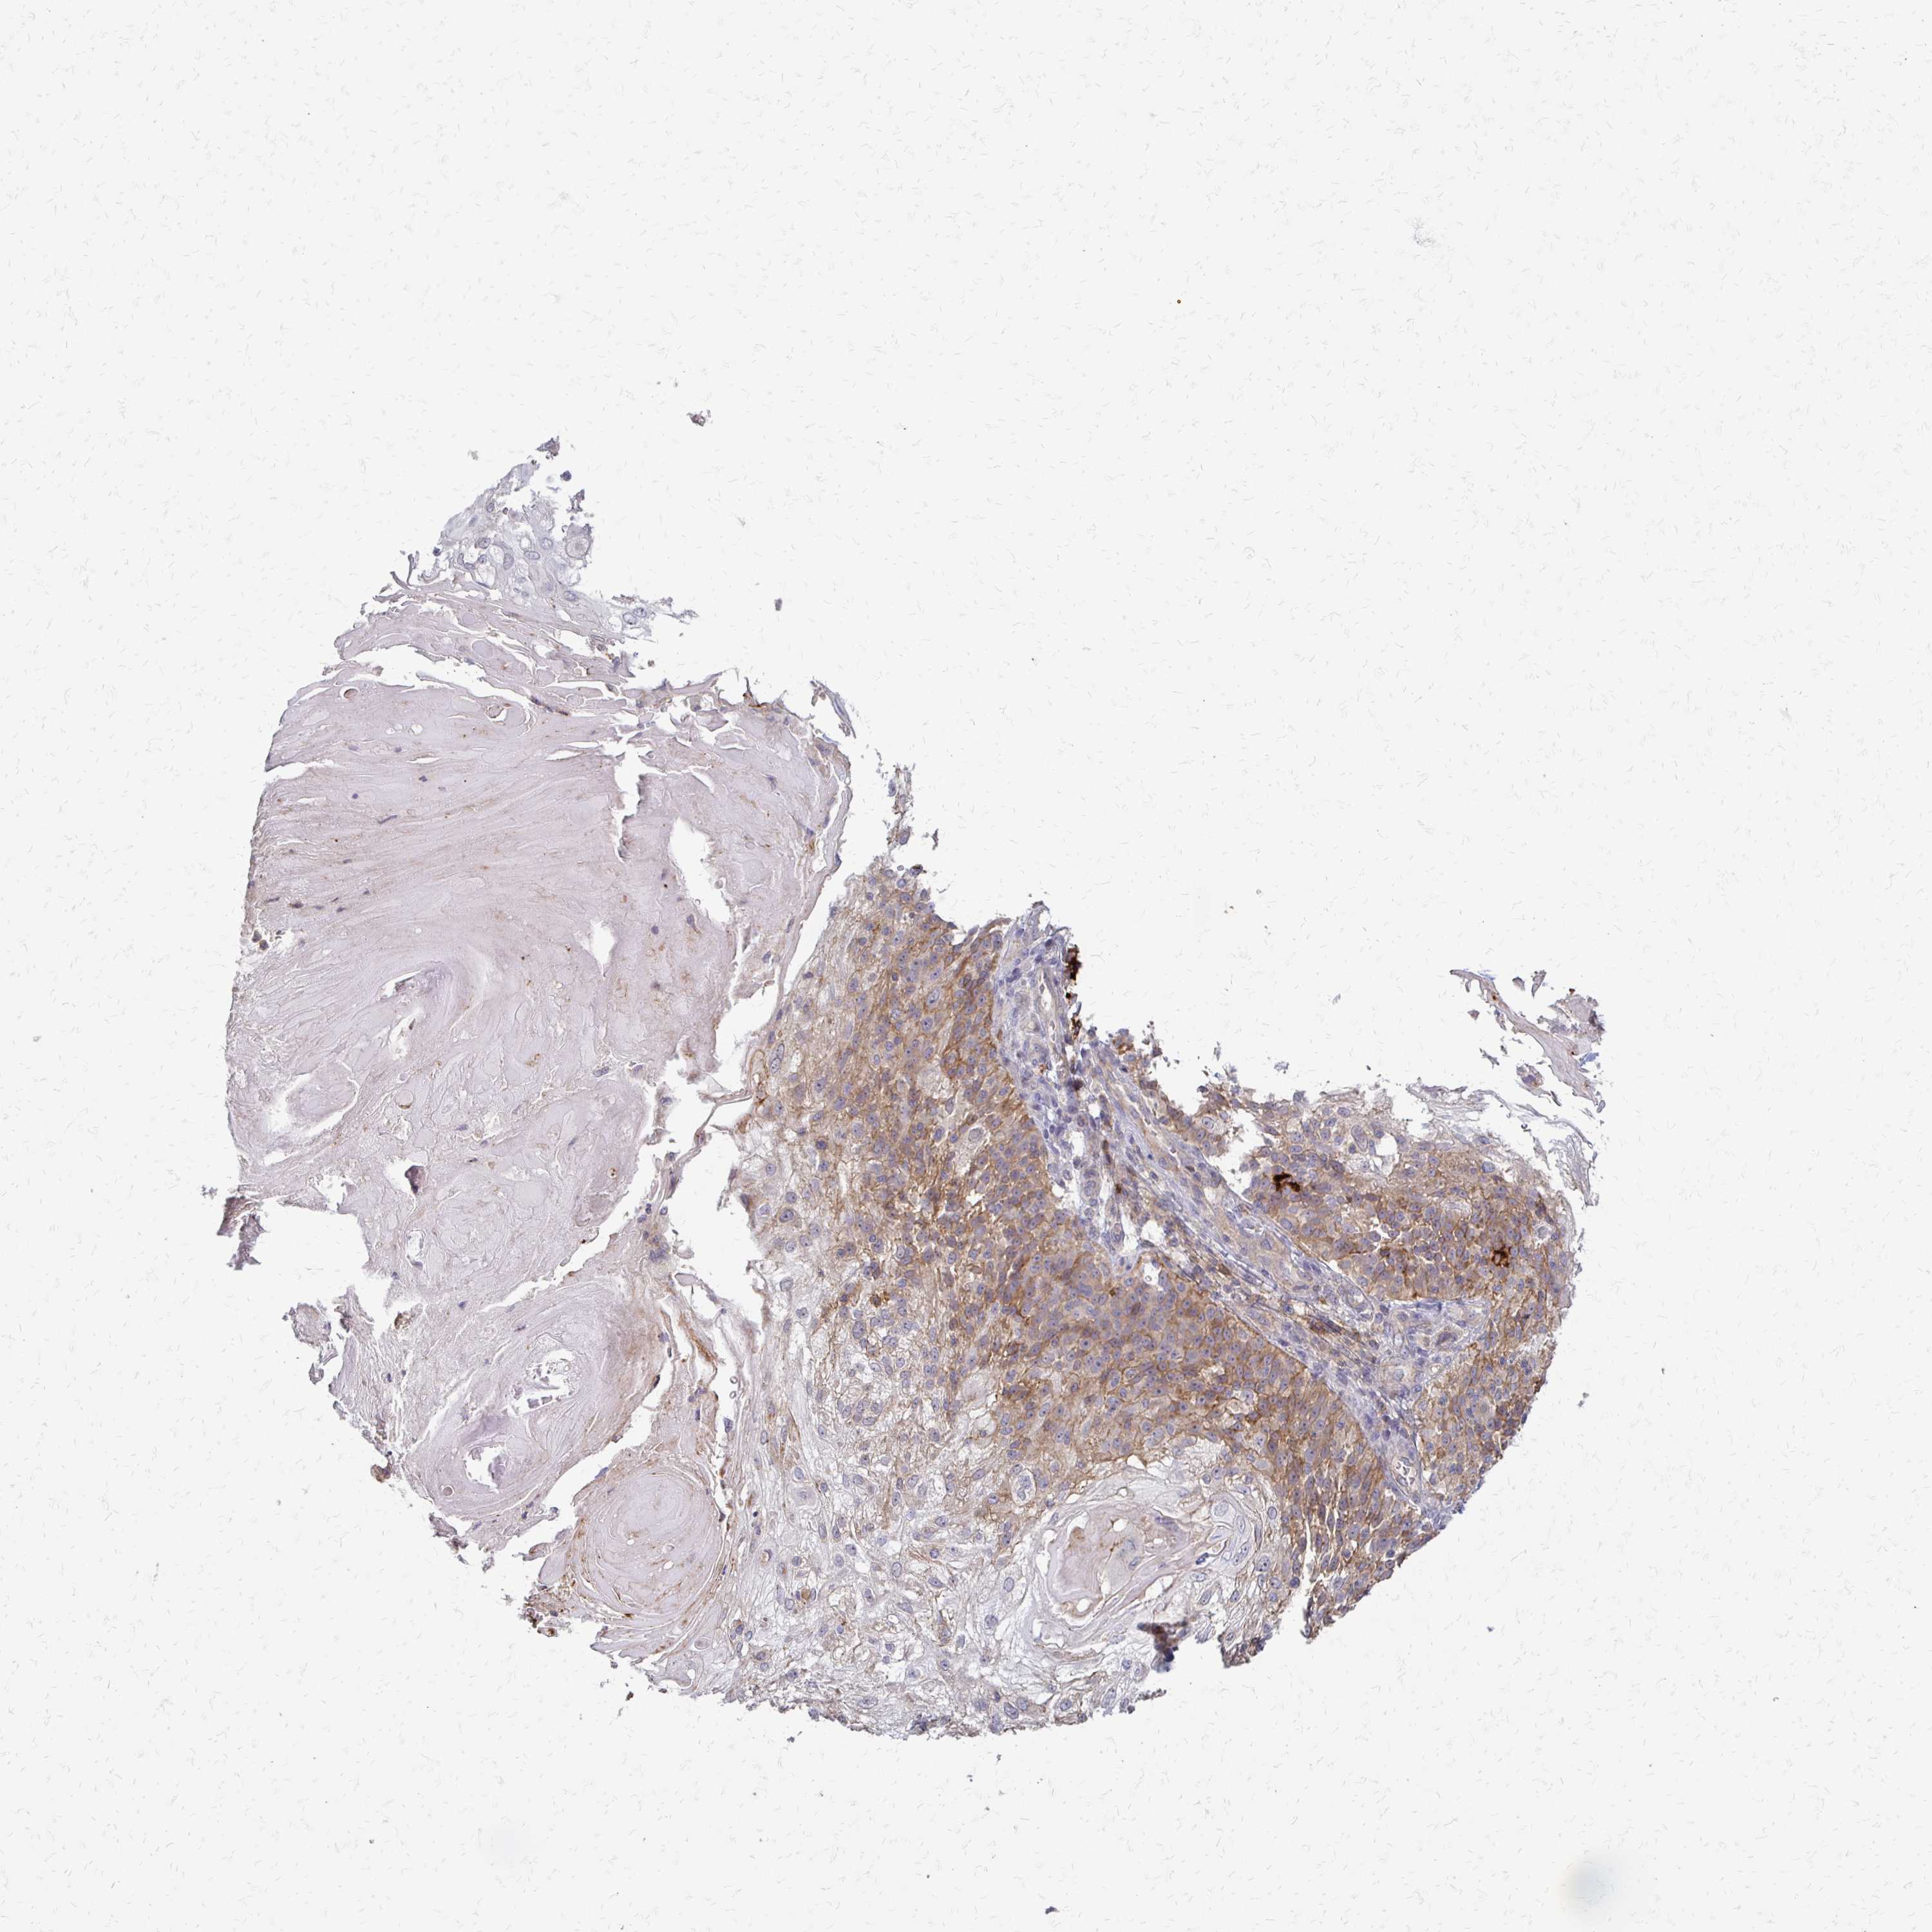

CANCER SKIN CANCER Show tissue menu

Basal cell and squamous cell cancer

SKIN CANCER - Protein expressioni

A mouse-over function shows sample information and annotation data. Click on an image to view it in a full screen mode. Samples can be filtered based on level of antibody staining by selecting one or several of the following categories: high, medium, low and not detected. The assay and annotation is described here.

Each image is clickable and will lead to virtual microscopy that enables deeper exploration of all samples and also displays staining intensity scores, fraction scores and subcellular localization as well as patient and tissue information for each sample.

Antibody HPA058234

Squamous cell carcinoma, NOS